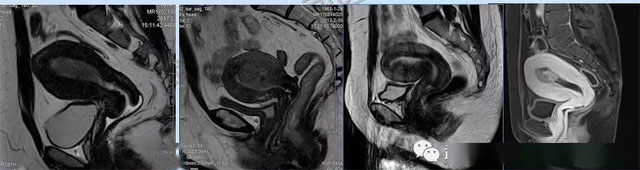

婦科疾病常常讓女性陷入了焦慮。主要是這類疾病婦女有難言之隱,癥狀隱匿,病情復(fù)雜。磁共振體檢車(chē)的金光火眼能力可以破解各種婦科難題。哪些情況需要使用磁共振檢查,檢查過(guò)程是否有不適。這些都是可以解決的。例如子宮常見(jiàn)疾病的磁共振診斷。

磁共振VS傳統(tǒng)檢查:有這些優(yōu)勢(shì)?無(wú)輻射安全系數(shù)高,磁共振沒(méi)有電離輻射,適合備孕跟孕婦檢查。它對(duì)軟組織有高清的成像效果,可以清晰的看到子宮各層的結(jié)構(gòu)??梢宰R(shí)別細(xì)小的肌瘤,早期的癌癥腫瘤。可以發(fā)現(xiàn)其他設(shè)備難以檢查到的深部子宮內(nèi)膜異位結(jié)節(jié)。多序列成像和增強(qiáng)掃描檢查,判斷腫瘤的良性準(zhǔn)確率高達(dá)90%以上。